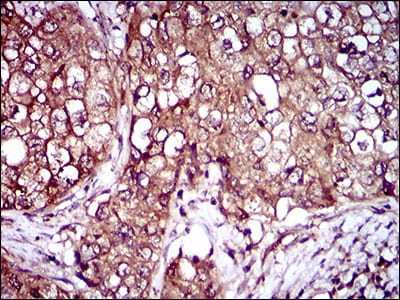

- Immunohistochemical analysis of paraffin-embedded human ovarian cancer tissues using IL3RA mouse mAb with DAB staining.

- Immunohistochemical analysis of paraffin-embedded human lung cancer tissues using IL3RA mouse mAb with DAB staining.